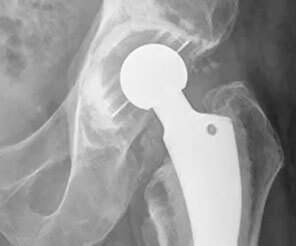

El reemplazo parcial de cadera remueve y reemplaza la cabeza del fémur del paciente, que es la bola en la parte superior del fémur, o hueso del muslo. No reemplaza el encaje. Una bola de cerámica o de metal se adjunta a la parte superior de un vástago que se inserta en el centro hueco del fémur. Los cirujanos suelen realizar esta cirugía para reparar ciertos tipos de fracturas de cadera.